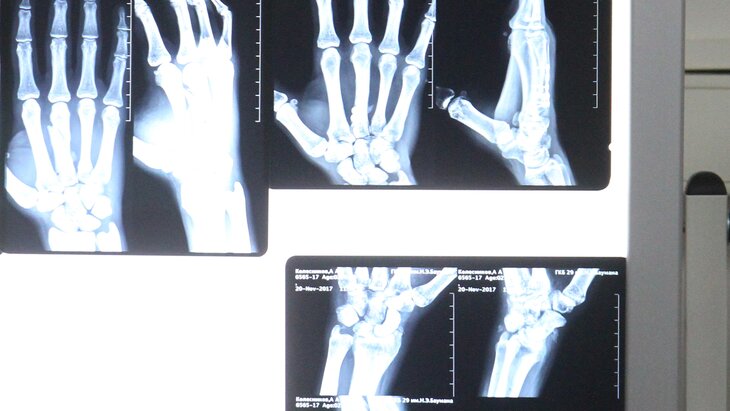

Подмосковные медики провели успешную операцию ребенку, пострадавшему в результате нападения обезьяны в деревне Терпигорьево. Об этом сообщила глава городского округа Мытищи Юлия Купецкая.

"Мама вместе с девочкой сейчас находится в реанимации под присмотром врачей, но уже завтра утром их переведут в обычную палату. Врачи провели своевременную операцию, подвижность ног не нарушена", – написала она в своем телеграм-канале.